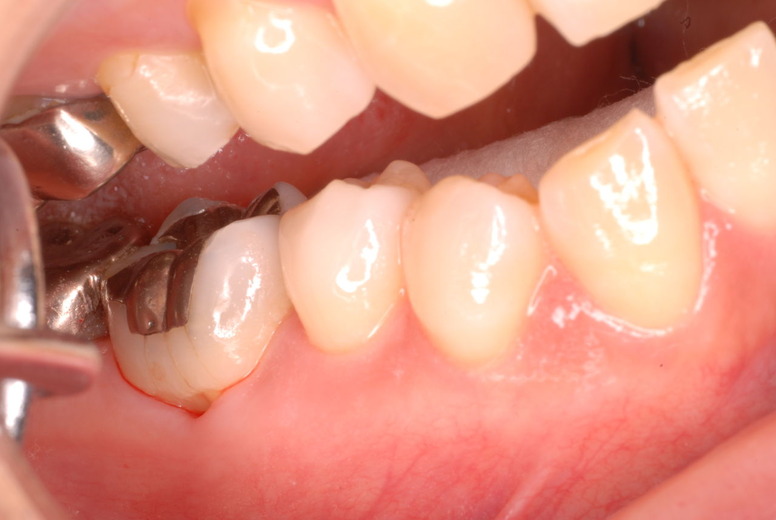

写真左下の親知らずが痛くなり抜歯しました。その後歯茎を除去して虫歯を露出させる処置を二回ほどしています。

レントゲンでは小さいですが、こう言う虫歯が一番怖いのです。

治療の成功率は極めて悪くすぐ再発しやすいのです。